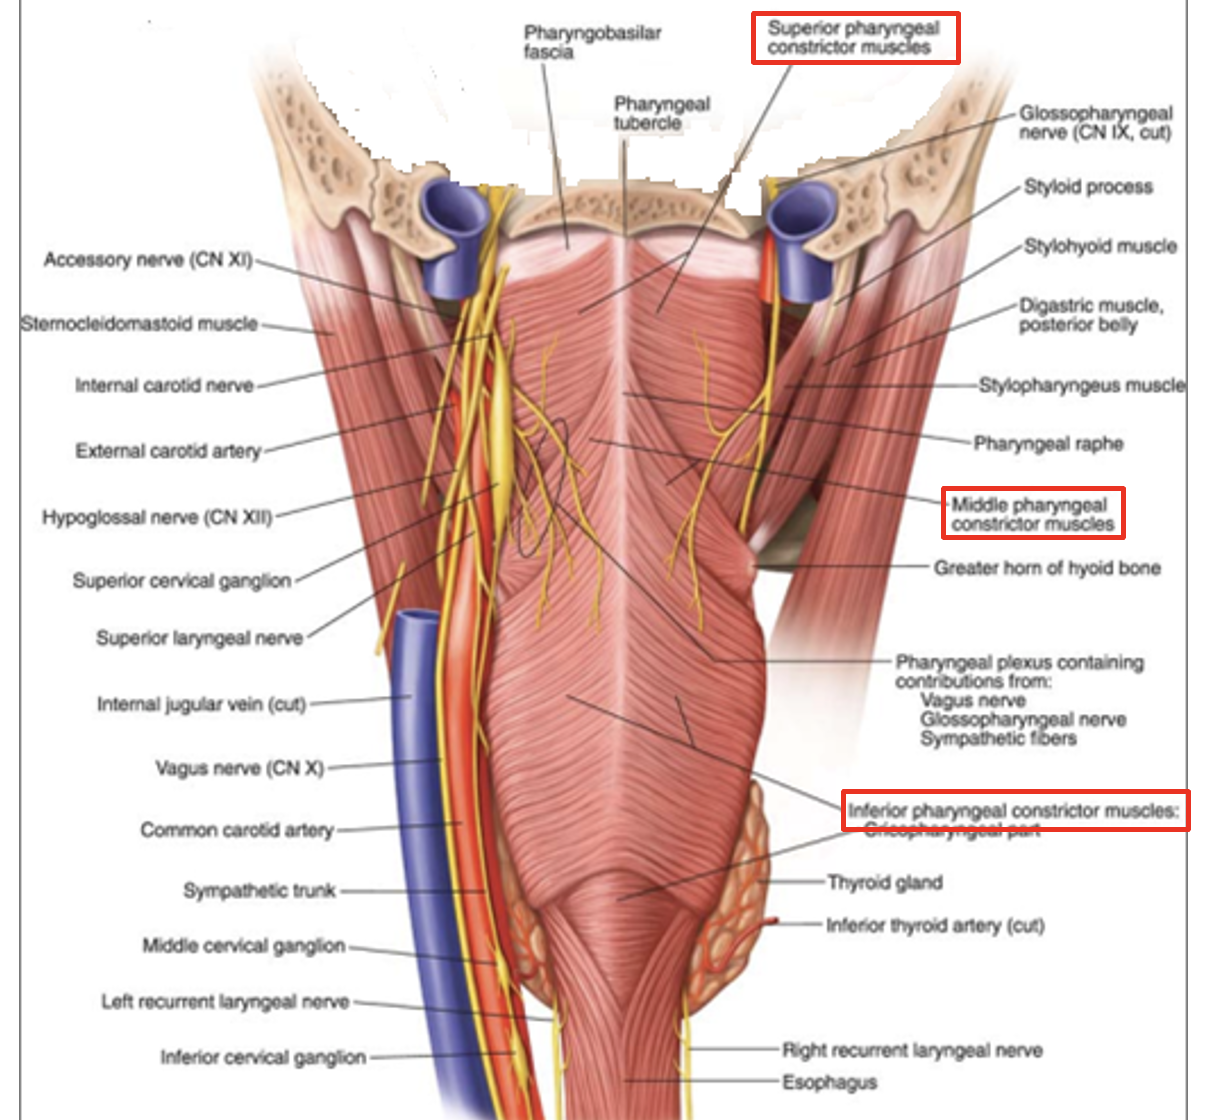

oropharynx: borders

oropharynx

from below the soft palate

to the tip of the epiglottis

oropharynx: how does it open into the mouth

via the oropharyngeal isthmus/ faucial isthmus

demarcated by the palatoglossal arch - anterior border of oropharynx

oropharynx: what does its lateral wall consist of

palatopharyngeal arch

palatine tonsil

tonsils: palatine tonsils location

palatine tonsils location

between the palatoglossal (anterior) and palatopharyngeal (posterior) arches

oropharynx